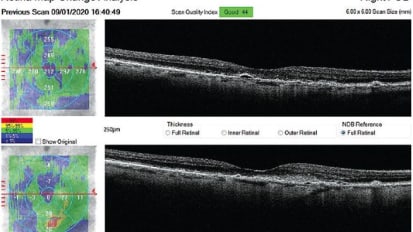

Use Your OCT’s Hood Report to Your Advantage

Change is Good